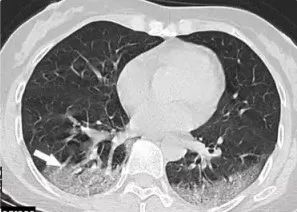

2. COVID-19进展期CT表现

病变进展,病灶增多、范围扩大。可累及多个肺叶,下叶居多。病灶变密实,境界不清,实性结节周围可环绕磨玻璃样渗出影呈“晕征”(如图2),部分表现为“反晕征”(图3,4)。病变周围小叶间隔可由于间质水肿而增厚,重叠于磨玻璃影上出现“铺路石征”(图5)。

图2 38岁女性,干咳4d,SARS-CoV-2核酸检测阳性,HRCT示左肺上叶两片斑片状磨玻璃样,境界不清,病灶中央密度增高,呈“晕征”改变

图3-4 22岁女性,干咳5d,SARS-CoV-2核酸检测阳性,HRCT示左肺下叶见两片斑片状混合密度影,境界不清,病中央密度稍低高,呈“反晕征”改变,伴有小叶间隔增厚(箭头所示)

图5 60岁女性,干咳5d,SARS-CoV-2核酸检测阳性,HRCT示左肺下叶斑片状密度增高影伴小叶间隔增厚“铺路石征”,病灶内可见增粗血管穿行(箭头所示)